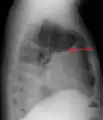

A pleural effusion as seen on lateral upright chest x-ray- Pleural effusion as seen behind the heart.[19]